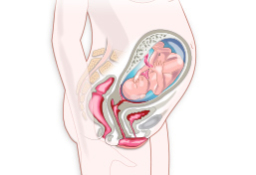

En el noveno mes de gestación, el cuerpo de la embarazada se prepara para el parto. El bebé ya se habrá encajado y es probable que la tripa, ya muy voluminosa, se note más baja. Algunas mujeres días antes de dar a luz expulsan el tapón mucoso. Cómo es una embarazada de 9 meses En el...